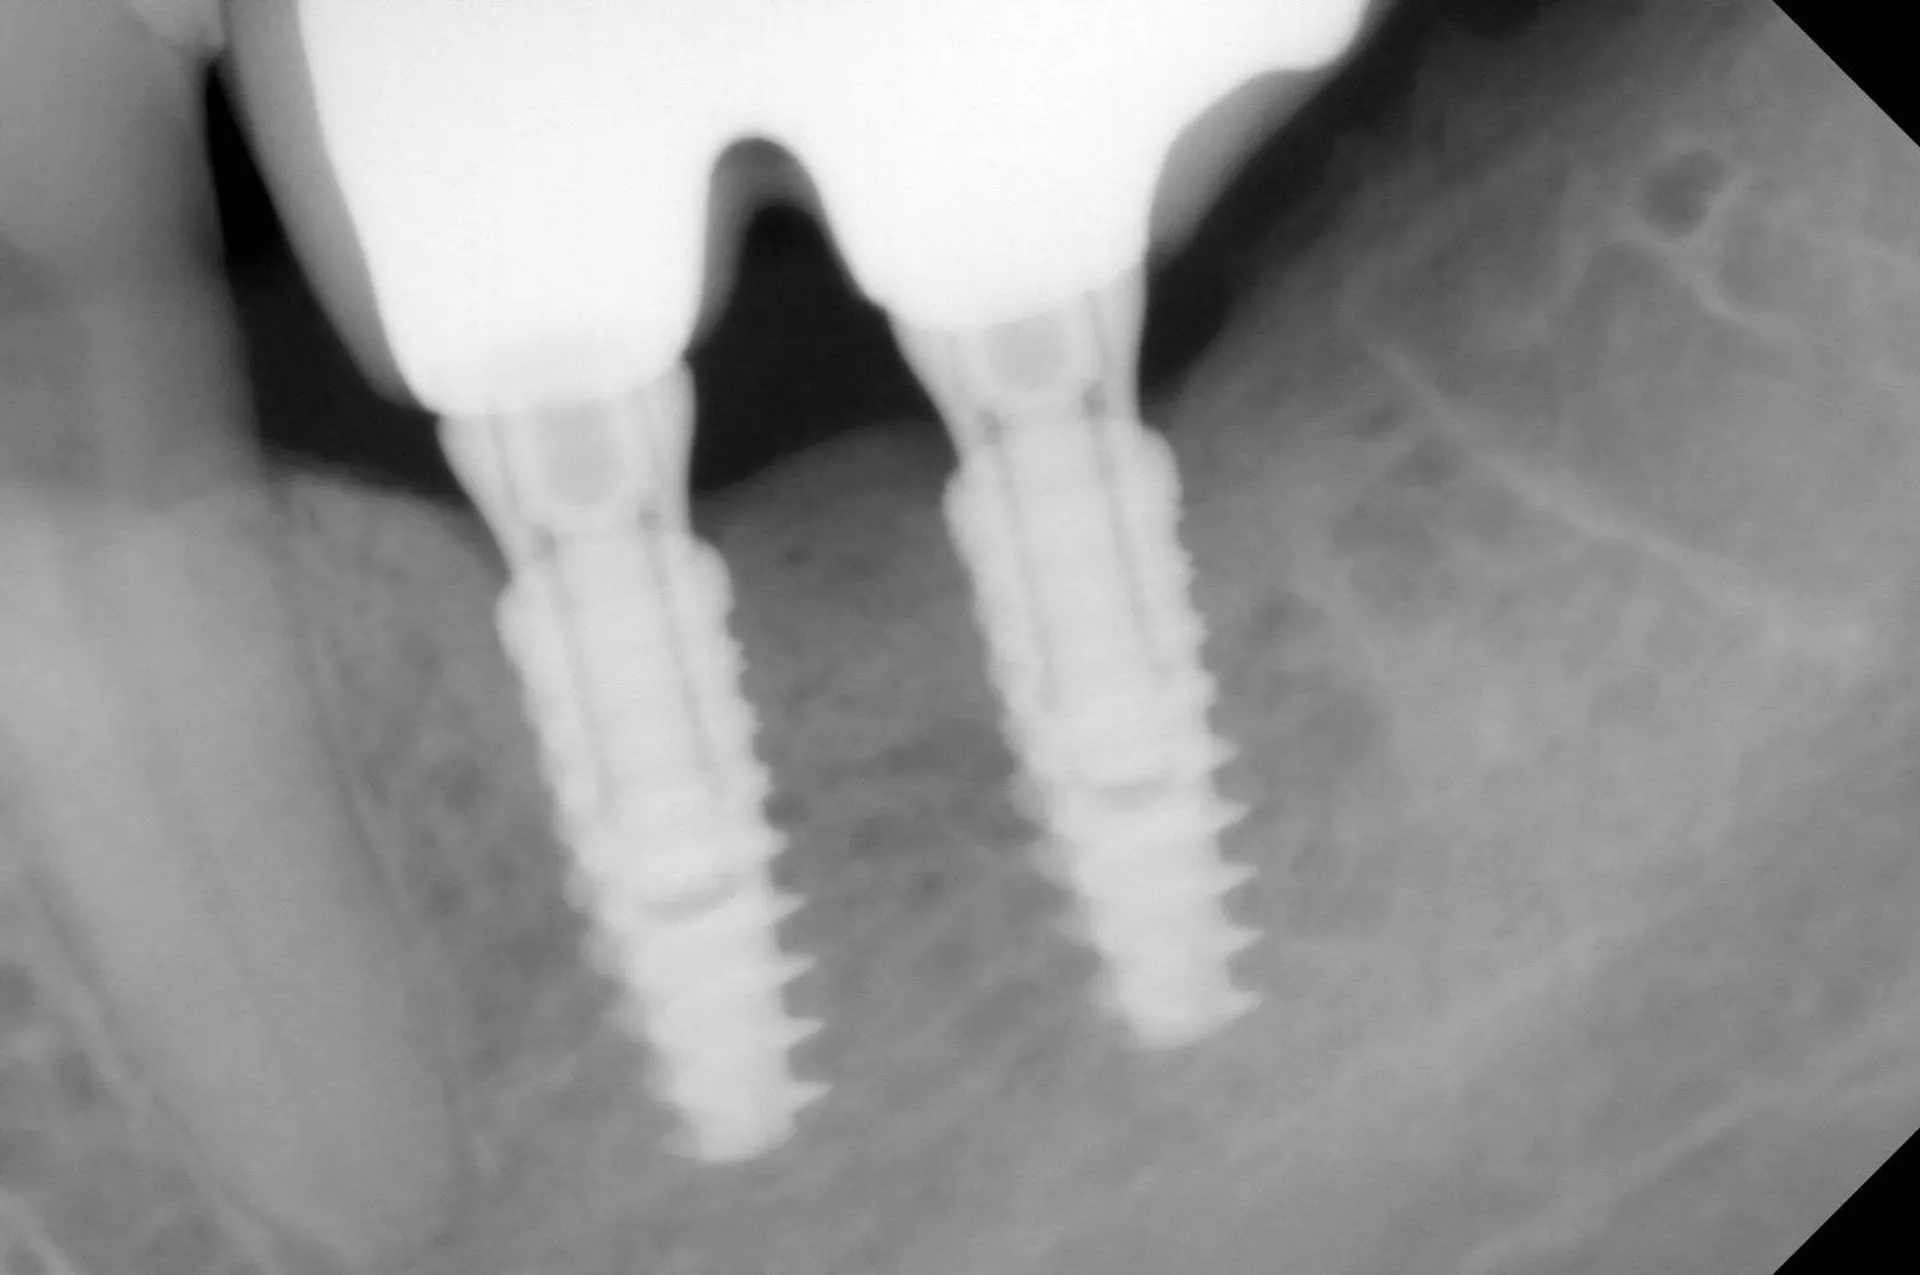

L'implant dentaire

est une racine artificielle en titane destinée a être inséré dans l'os de la mâchoire.

Il supporte ensuite une

prothèse dentaire

ou

couronne

afin de remplacer la dent absente.

La pose d'implants dentaires est en général une chirurgie légère qui engendre des suites opératoires faibles.

Selon la qualité de l'os et la technique utilisée la durée du traitement peut aller de quelques jours a plusieurs mois.